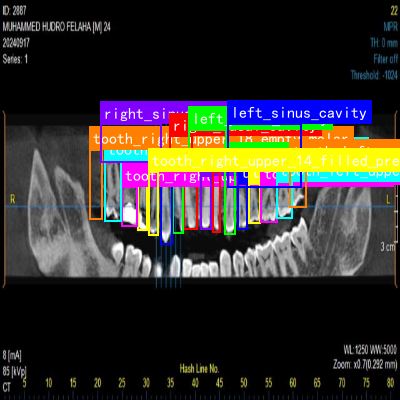

检测结果采用边界框和掩膜形式标注在原始图像上,每个边界框对应一个检测到的颌骨结构。边界框的颜色根据类别自动分配,不同结构使用不同颜色,便于区分。边界框上方显示类别名称和置信度百分比,让医生了解识别结果的可靠性。

对于牙齿状态识别,系统还会特别标注出异常情况,如龋齿、牙周炎等病变区域,并用不同颜色标记严重程度。这种直观的可视化方式帮助医生快速识别问题区域,提高诊断效率。

图片展示了口腔颌骨区域的医学影像切片,共6张排列成2行3列。每张切片呈现颌骨及周围软组织的横断面或矢状面解剖结构,可见骨骼的密度差异、牙槽骨形态及邻近软组织轮廓。图像中存在标注元素(如绿色标记),可能用于指示特定解剖结构或病变位置;部分切片显示牙齿与颌骨的位置关系,可观察到牙根形态、牙周间隙等细节。这些影像是口腔颌骨多结构分割的基础数据------通过分析不同组织的灰度、边界特征,可实现颌骨、牙齿、牙周膜等结构的精准分割;同时,结合牙齿在影像中的位置、形态完整性及周围骨质变化,能辅助判断牙齿萌出状态、龋坏程度、根尖周病变等信息,为口腔疾病的诊断与治疗规划提供依据。

DentalProject3是一个专注于口腔颌骨区域分割与牙齿状态识别的专业数据集,采用CC BY 4.0许可证授权。该数据集于2025年5月7日通过qunshankj平台导出,包含272张经过预处理的牙科CT影像图像,所有图像均被调整为640×640像素尺寸,并进行了自动方向校正和EXIF方向信息剥离处理。数据集采用YOLOv8格式标注,共包含174类解剖结构和牙齿状态标签,涵盖了双侧下颌管、鼻腔、上颌窦等主要颌骨区域,以及上下颌各牙齿(从第三磨牙到第三磨牙)的完整分类,每颗牙齿均标注了空缺、填充和种植体三种状态,并包含截面分割信息。数据集按训练集、验证集和测试集进行划分,为口腔医学影像的自动化分析提供了高质量的标注资源,特别适用于牙齿状态评估、颌骨结构分割以及口腔种植术前规划等计算机视觉任务。